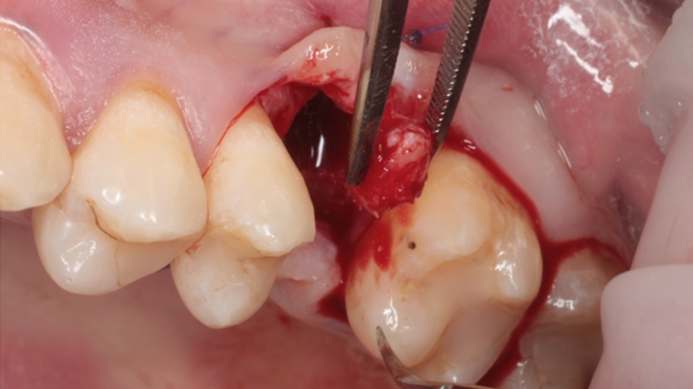

Clinical case: # 46 implant placement & GBR using i-Gen membrane for significant vertical resorption & mixed bone defect

- Courtesy of Dr. Iulian Filipov, Romania -

AnyRidge, mandibular posterior, i-Gen, resorption, bone defect, bone regeneration, space management, #46, GBR, Dr. Iulian Filipov

AnyRidge implant system, i-Gen